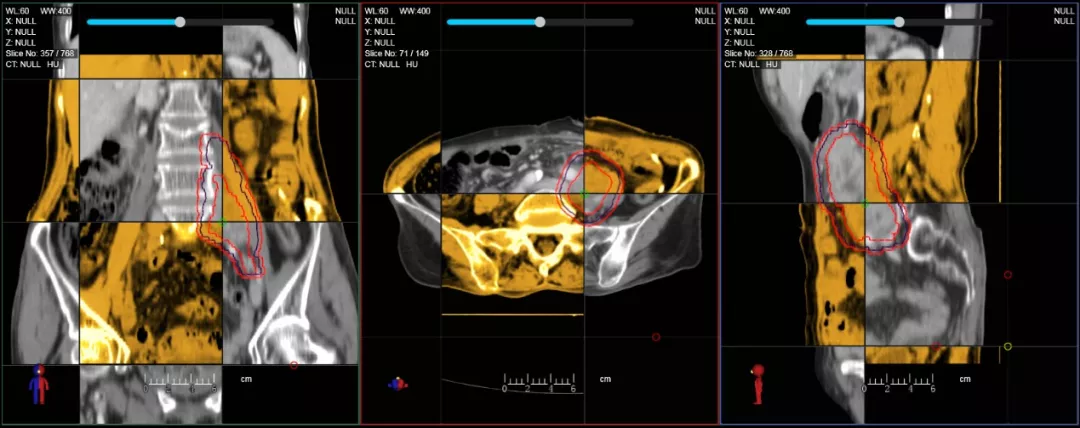

CT-IGRT配準(zhǔn),除骨性標(biāo)記外,還能以器官、軟組織等作為參考,真正找到配準(zhǔn)目標(biāo)